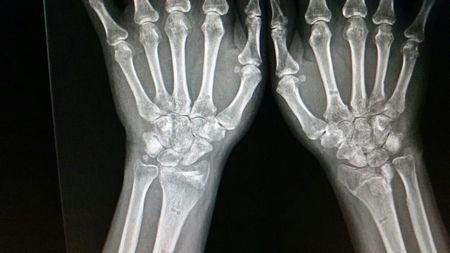

右手手腕骨裂图片,手腕骨折的真实图片

手腕骨折的真实图片

手腕骨裂

骨折和骨裂的图片